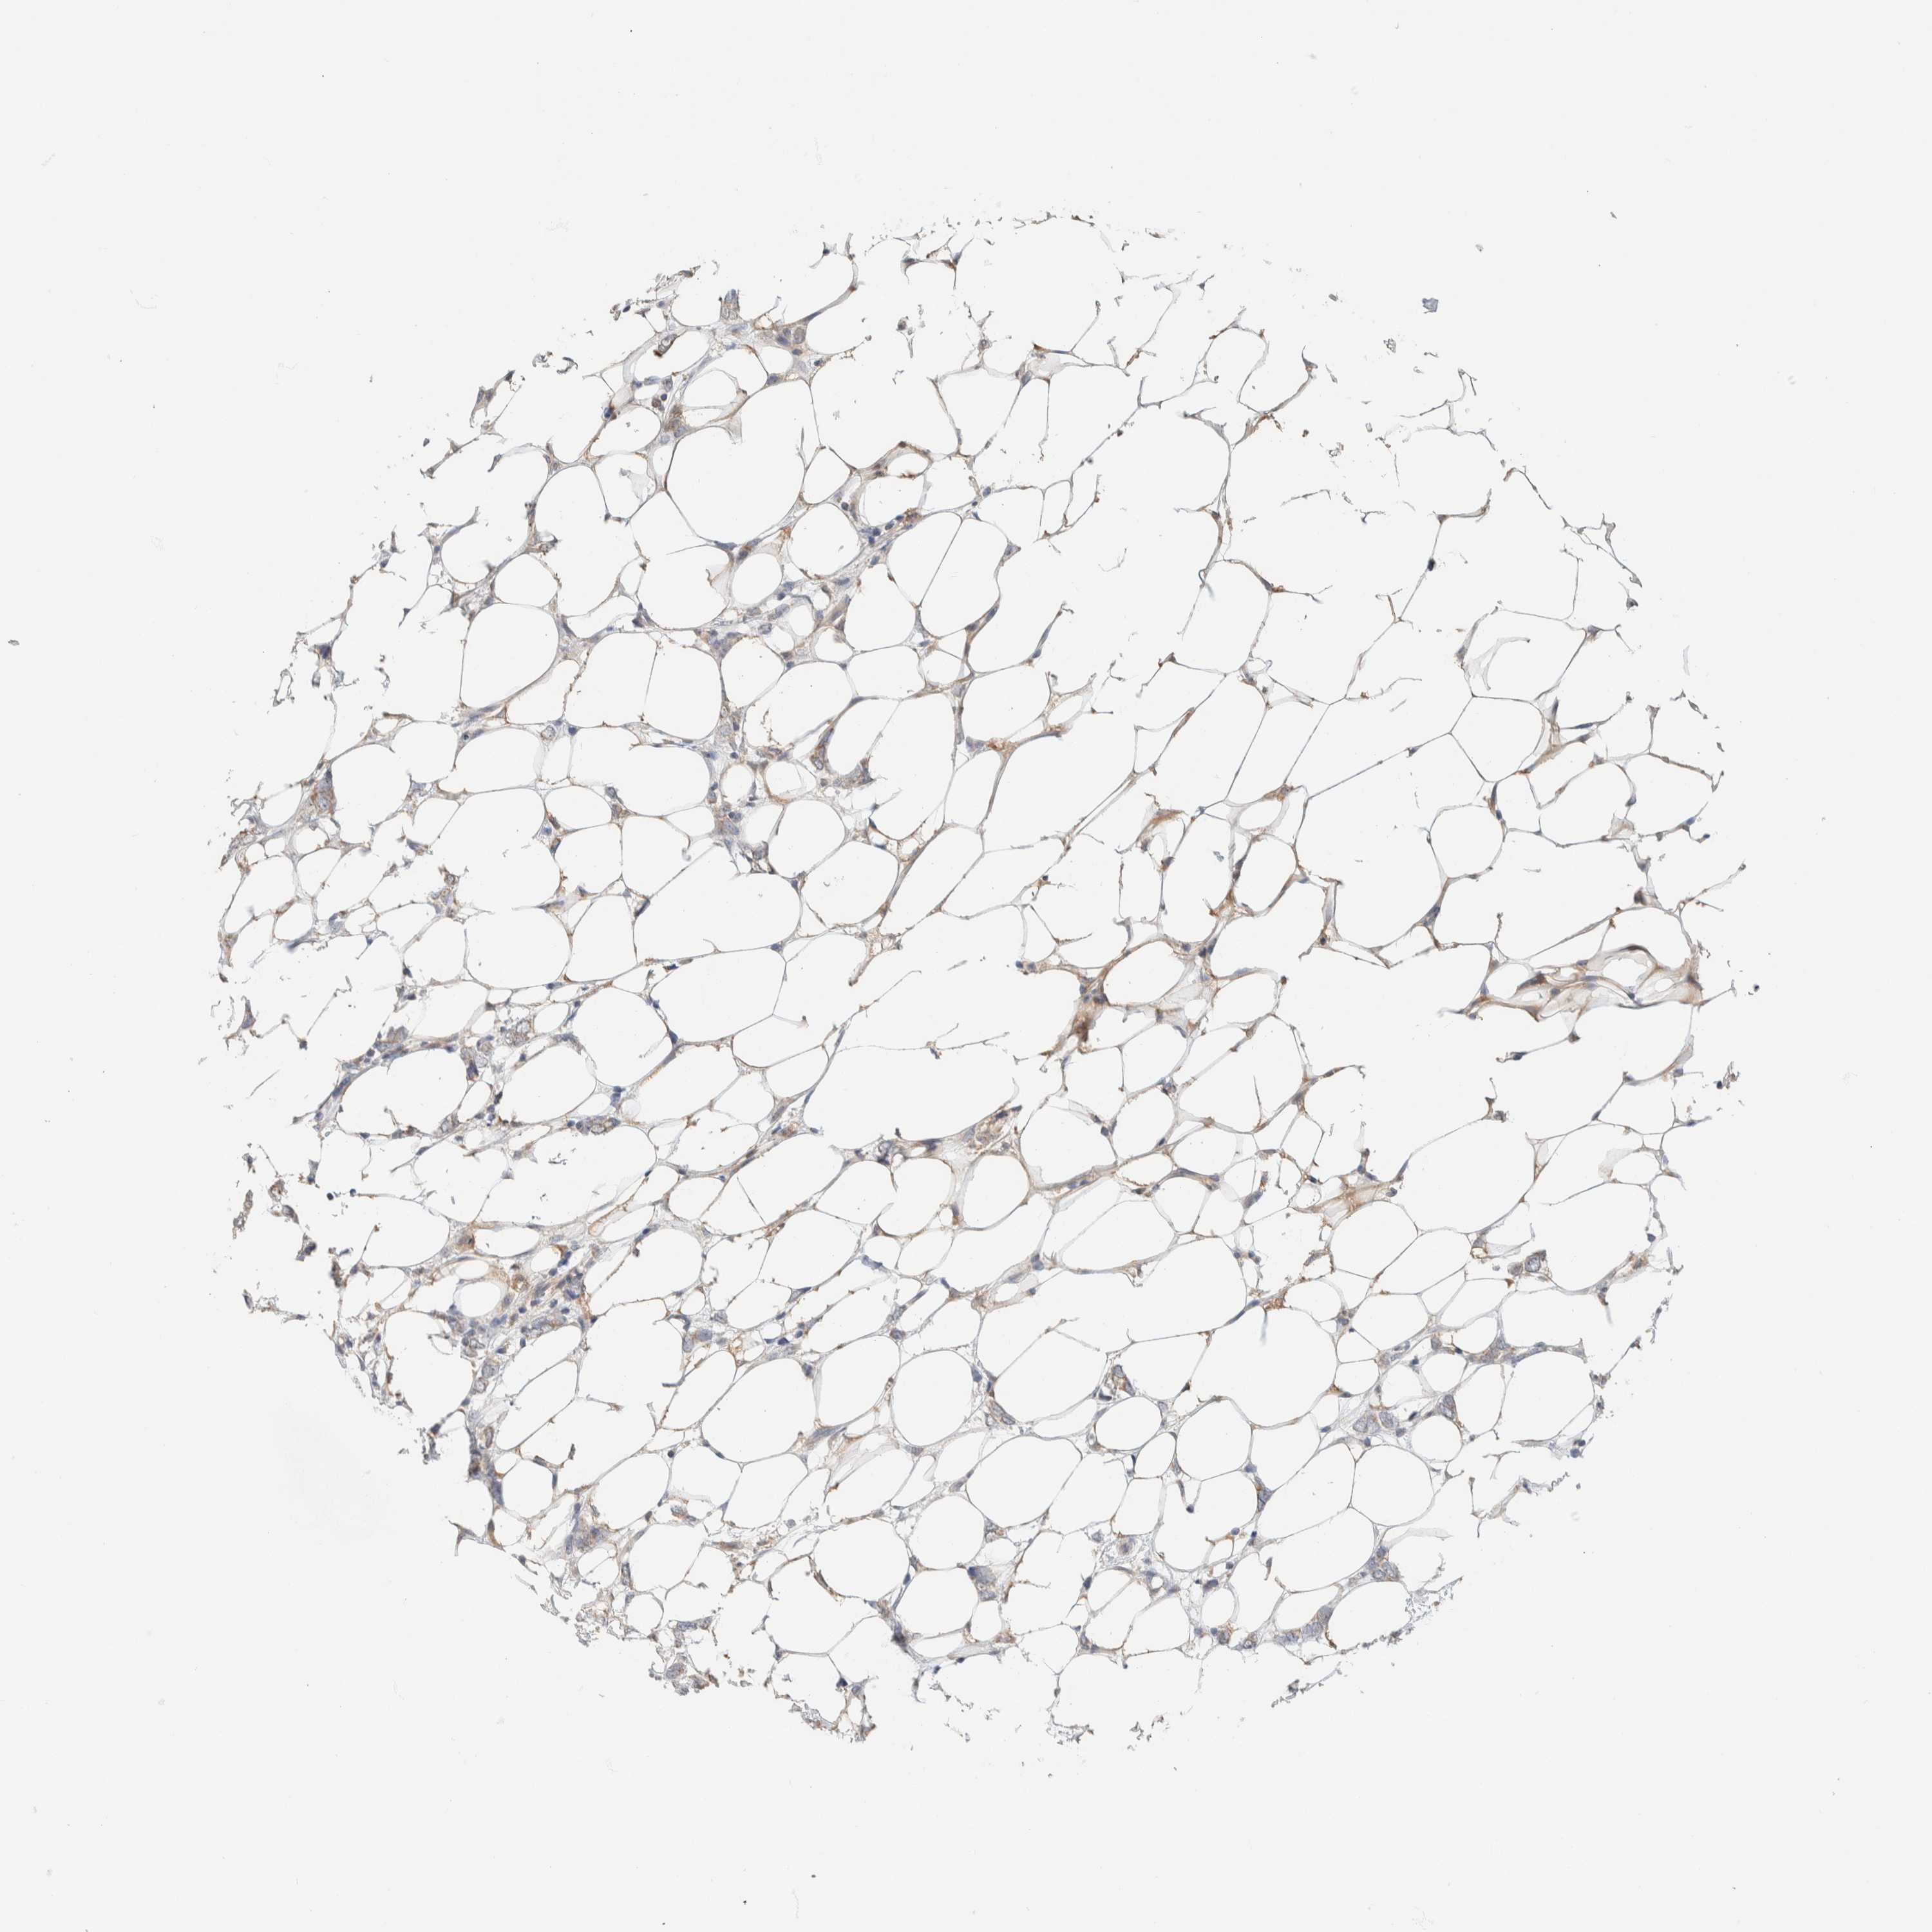

BRCA TCGA BRCA VALIDATION PROTEIN EXPRESSION